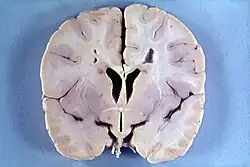

Many people with abnormally large heads or large skulls are healthy, but macrocephaly may be pathological. Pathologic macrocephaly may be due to megalencephaly (enlarged brain), hydrocephalus (abnormally increased cerebrospinal fluid), cranial hyperostosis (bone overgrowth), and other conditions. Pathologic macrocephaly is called "syndromic", when it is associated with any other noteworthy condition, and "nonsyndromic" otherwise. Pathologic macrocephaly may be caused by congenital anatomic abnormalities, genetic conditions, or by environmental events.[2]

Many genetic conditions are associated with macrocephaly, including familial macrocephaly related to the holgate gene, autism, PTEN mutations such as Cowden disease, neurofibromatosis type 1, and tuberous sclerosis; overgrowth syndromes such as Sotos syndrome (cerebral gigantism), Weaver syndrome, Simpson–Golabi–Behmel syndrome (bulldog syndrome), and macrocephaly-capillary malformation (M-CMTC) syndrome; neurocardiofacial-cutaneous syndromes such as Noonan syndrome, Costello syndrome, Gorlin syndrome,[3] (also known as basal cell nevus syndrome) and cardiofaciocutaneous syndrome; Fragile X syndrome; leukodystrophies (brain white matter degeneration) such as Alexander disease, Canavan disease, and megalencephalic leukoencephalopathy with subcortical cysts; and glutaric aciduria type 1 and D-2-hydroxyglutaric aciduria.[2]